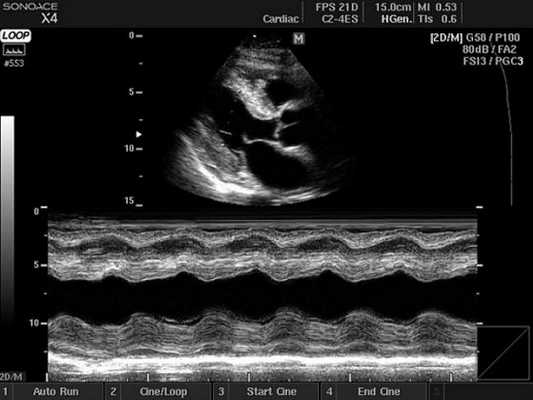

- Двухмерный (2D режим). На монитор выводится изображение сердца в разрезе (в двух измерениях). Данный способ является основным при визуализации этого органа, позволяет детально рассмотреть анатомические отклонения и аномальные движения миокарда, клапанов.

- М-режим (M-mode). Это «усеченный» вариант предыдущего, при котором используется для анализа только одномерное изображение. Основное внимание уделяется одной из линий 2D трассировки, что позволяет более детально исследовать движения створок клапанов и сердечной мышцы.